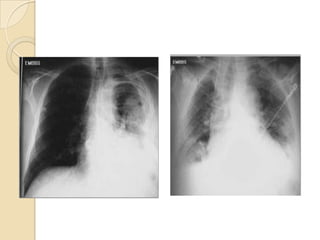

Rx. Tórax PA. (A). posterior a la                 Rx. Tórax PA.(B). Disminución de los      Rx. Tórax PA.(C). Aumento

insercion del tubo de tórax para                  espacios intercostales izquierdos,        compensatorio del volumen

drenaje pleural. radiopacidad difusa              engrosamiento pleural severo ,            pulmonar derecho, mayor

del hemitórax izquierdo, con colapso              borramiento de los senos costo-           aclaramiento del vértice y

parcial pulmonar, desviación                      frénicos, elevación hemi-diafragma        disminución de espacios

mediastinal hacia la derecha. Por                 izquierdo.escoliosis dorsal leve y poco   intercostales del hemitórax izquierdo.

proceso neumonico con derrame                     aclaramiento del vertice porfibrosis      retracción del diafragma izquierdo,

pleural.                                          pleural y atelectasia pulmonar.           escoliosis marcada por fibrotorax